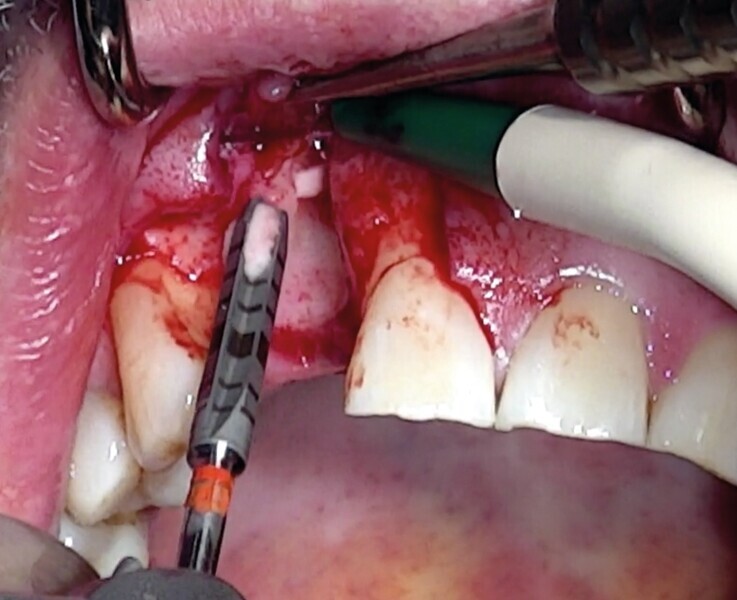

Une fracture radiculaire de 22 a lésé la table osseuse vestibulaire et la gencive en regard. Elle est extraite minutieusement à l’aide du Benex (Fig. 19). Un curetage de l’alvéole est réalisé manuellement puis au contra-angle, à l’aide d’une fraise boule multilame de gros diamètre. Un lambeau de pleine épaisseur est soulevé (Fig. 20).

Comme la technique initiale, le défaut osseux est calibré par un trépan (Fig. 21) d’extraction-implantation immédiate, plus apicale que l’apex de l’alvéole dentaire et aux dépens de la corticale palatine.